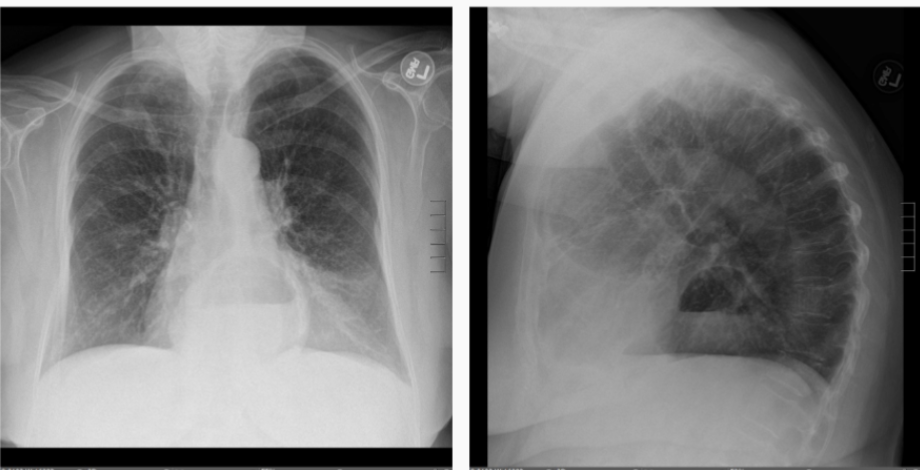

Which image represents the “spine sign” and what does this mean?

Right side is spine sign; means that there is something in the lungs (should go bright—>dark, not dark—>bright)